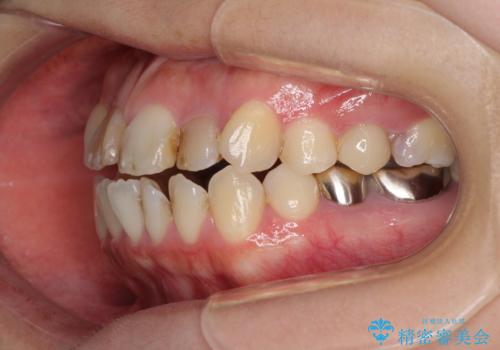

上顎前歯や下顎大臼歯に根管治療の必要な歯がいくつかあるため、矯正治療と並行して根管治療を行い、その後オールセラミッククラウンにて補綴治療を行うこととしました。